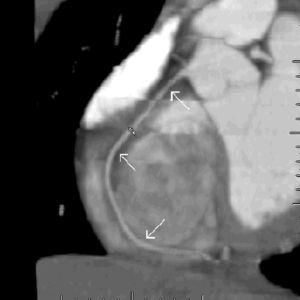

Se muestran las imágenes del árbol coronario que permiten descartar anomalías en esta localización. La figura 1 muestra una proyección axial de máxima intensidad (MIP) de la salida de las arterias coronarias. La figura 2 es una proyección coronal de máxima intensidad (MIP) de la arteria coronaria derecha similar a la proyección oblicua anterior derecha de la angiografía. Las figuras 3 y 4 son reconstrucciones en volume rendering en proyección oblicua anterior izquierda del tronco coronario izquierdo y su bifurcación y de la base del corazón, en la que se visualiza la salida del tronco coronario izquierdo. Se han retirado las venas pulmonares izquierdas. En la estación de trabajo, mediante el análisis avanzado de vasos se puede visualizar un vaso tortuoso o de trayecto curvo en un solo plano tomográfico permitiendo una cuantificación de la lesiones estenóticas. El estudio no detectó anomalía en la anatomía ni estenosis coronaria significativa en el paciente.

Figura 2. Proyección coronal de máxima intensidad de la arteria coronaria derecha similar a la proyección oblicua anterior derecha de la angiografía.